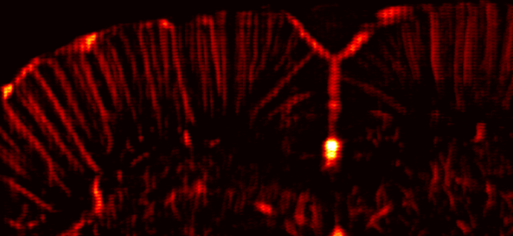

(c) In vivo RF frame

(d) In vivo RF magnified

(e) In vivo B-mode frame

Refer to caption 3 mmtimes3millimeter3\text{\,}\mathrm{mm}start_ARG 3 end_ARG start_ARG times end_ARG start_ARG roman_mm end_ARG

Refer to caption

(a) In silico RF test frame

(b) In silico RF magnified

(f) B-mode magnified

Figure 6: SG-SPCN localization results, which are visually highlighted as red blobs overlaid on synthetic and real frames. Blue rectangles indicate the magnified region. The images in (6) to (6) are from rat-18 frame index 2400 at R=12𝑅12R=12italic_R = 12. The results show our network’s ability to transfer knowledge from synthetic RF data to unseen in vivo frames.